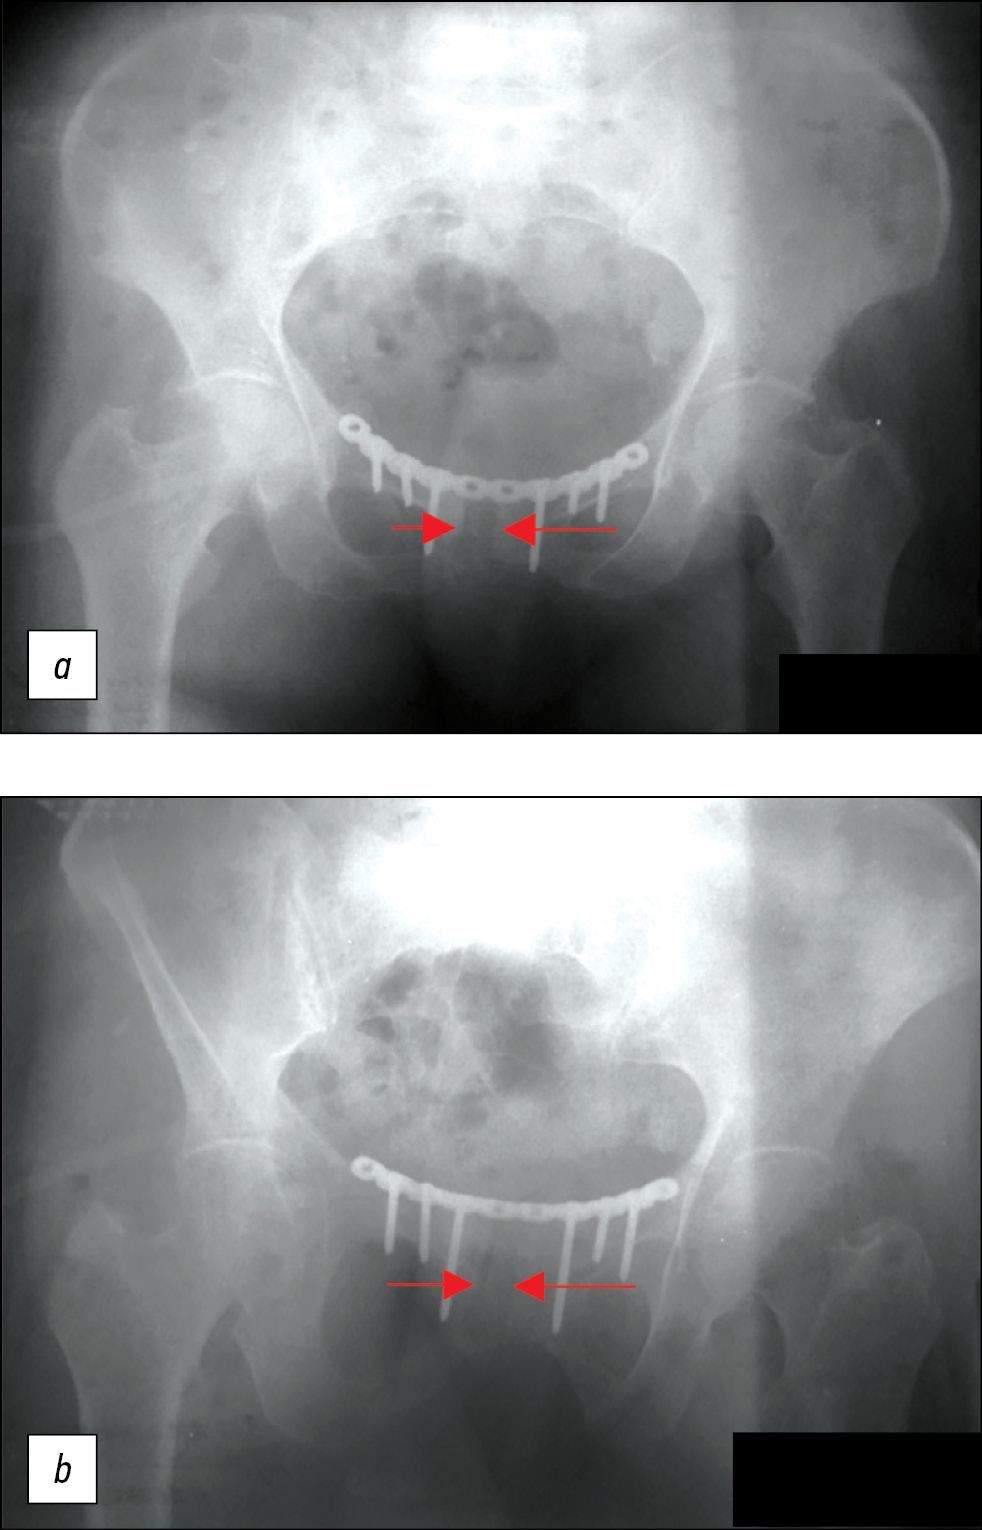

Рис 1. Пациентка 60 лет на рентгенограммах перелом правой лобковой кости, призна-ки узурации лонного сочленения. (а – передне-задняя проекция, б – краниальная проекция)

Fig. 1. A 60-year-old patient on radiographs shows a fracture of the right pubic bone, signs of pubic symphysis occlusion. a — anterior-posterior projection, b — cranial projection.

На компьютерной томограмме (КТ) костей таза от 26.02.2020: перелом ветвей правой лонной кости на уровне лонного сочленения, признаки консолидации не выражены (рис. 1, 2).

На рентгенограммах от 02.03.2020: узурация зоны лонного сочленения (см. рис. 1).